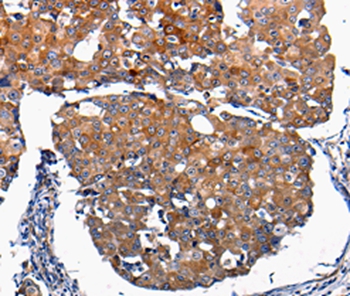

Immunohistochemical analysis of paraffin-embedded Human breast cancer tissue using #36769 at dilution 1/100.

Immunohistochemistry: 1:100-1:500